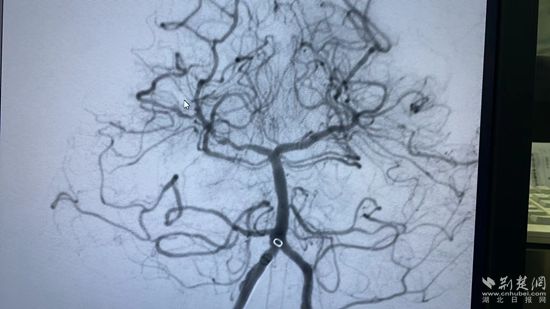

患者的再次DSA造影顯示:基底動脈閉塞。在場所有醫(yī)護(hù)都倒吸了一口冷氣,患者吳老太太命懸一線。

更讓人糾心的是:患者椎動脈開口血管極其彎曲,給取栓手術(shù)增加了極大的阻力。該院神經(jīng)內(nèi)科介入團(tuán)隊(duì)精心配合,謹(jǐn)慎操作,終于將微導(dǎo)管及取栓抽吸導(dǎo)管沿這“山路十八彎”的管路到達(dá)閉塞的血管處,飛利浦C臂高清透視下精準(zhǔn)到位抽吸導(dǎo)管連接抽吸注射器,一枚7毫米 X 3毫米大小血栓奇跡地抽出體外。

再次造影顯示,血栓抽吸成功,閉塞血管開通了!